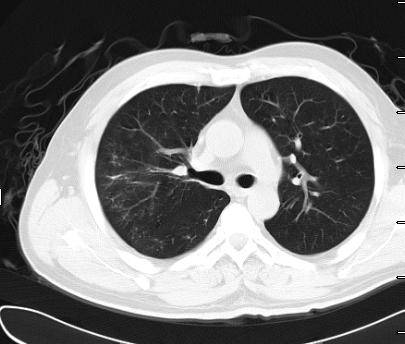

患者3月15日无明显诱因出现咳嗽、咳白粘痰,伴乏力、咽痛、周身酸痛,自服感冒药、阿奇霉素症状减轻;18日出现发热,最高39.4℃,伴畏寒,无寒战,稍感胸闷气短,当地医院予复方氨林巴比妥、利巴韦林、热毒宁治疗,体温降至正常。19日出现咯血,为鲜红色,量约30ml,上述症状较前加重,20日再次就诊于当地医院,行肺CT(图一)示“双肺炎”,遂转入我院急诊。既往高血压病史2年,无烟酒嗜好。

(图一)